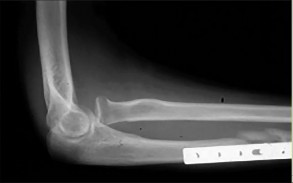

- الأشعة السينية (X-rays): هي الخطوة الأولى في تقييم الكسور، الخلوع، وتغيرات التهاب المفاصل. تساعد في تحديد مدى تدهور العظام والمسافات المفصلية. على سبيل المثال، تُظهر صور الأشعة السينية كسور السلاميات

. - الأشعة المقطعية (CT Scan): توفر صوراً تفصيلية ثلاثية الأبعاد للعظام، وهي مفيدة جداً لتقييم الكسور المعقدة، مثل كسور العظم الخطافي (Hamate Hook Fracture) التي قد لا تظهر في الأشعة السينية العادية

، أو لتقييم مدى تدهور العظم في حالات مثل مرض كينبوك. - التصوير بالرنين المغناطيسي (MRI): ممتاز لتقييم الأنسجة الرخوة مثل الأربطة، الأوتار، الأعصاب، والعضلات. يكشف عن التمزقات،